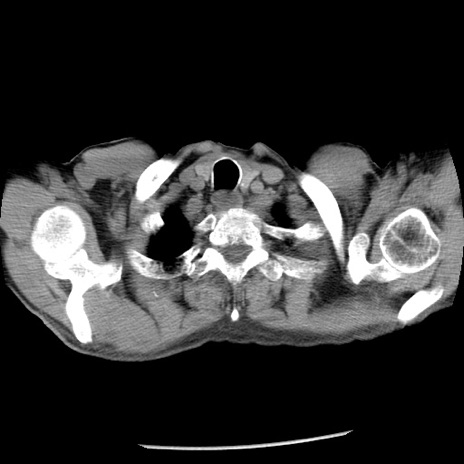

症例26(横断像)

【症例】80歳代男性

【主訴】嘔吐

【現病歴】昨晩2回嘔吐あり、今朝になっても嘔吐あり。来院。

【既往歴】胃潰瘍

【身体所見】意識清明、BT 37.6℃、BP 166/95mmHg、HR 100bpm、SpO2 97%、腹部:平坦・軟、腸蠕動音聴取良好、圧痛なし。

【データ】WBC 21900、CRP 1.46